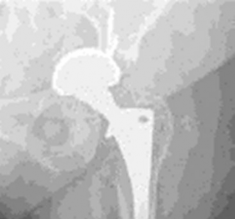

4. Proximal Femoral Reconstruction (Paprosky Type II/IIIA):

• Highly Porous Sleeves: For significant metaphyseal bone loss and widened canals (Paprosky Type II and IIIA), HPM sleeves are frequently used. These sleeves are press-fit into the proximal femur, providing robust metaphyseal fill and immediate stability through hoop stress. They are often fixed with screws if additional stability is needed.

• A modular tapered stem (often coated with HPM for ingrowth) is then inserted through the sleeve, engaging distal diaphyseal bone. This construct allows for independent adjustment of leg length and offset.